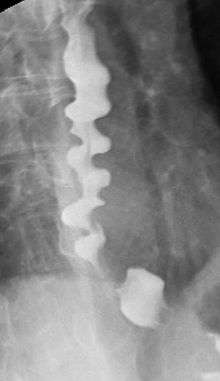

Corkscrew appearance of the esophagus.

Several radiographic findings are suggestive of DES, such as a "rosary bead esophagus" or "corkscrew" appearance on barium swallow x-ray, although these findings are not unique to DES.[1]